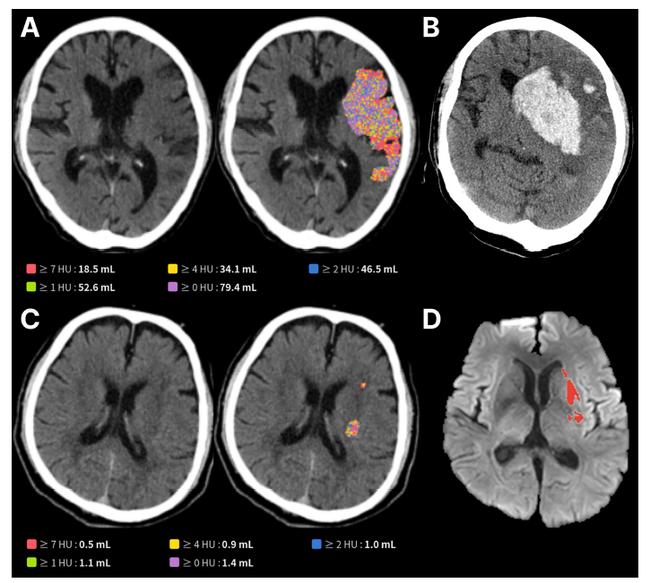

AI 뇌경색 최신 연구 'Frontiers in Neuroscience' 논문 발표 자료

의료 AI 전문기업 제이엘케이가 개발한 뇌경색 병변 검출 AI 모델이 대규모 임상 검증을 통해 신뢰성을 입증했다.

이번 성과는 SCI급 국제학술지 ‘Frontiers in Neuroscience(IF=0.77)’에 게재돼 기술적 가치를 국제적으로 인정받았다. 제이엘케이는 이 모델이 뇌 손상 범위를 정량화할 뿐 아니라 환자의 기능적 회복 가능성과 합병증 위험까지 예측할 수 있음을 확인했다고 밝혔다.

일반적으로 뇌졸중 환자는 응급실에서 NCCT 검사를 먼저 받지만, 초기 병변은 미세해 육안으로 정확히 판별하기 어렵고 의료진 경험에 따라 진단 차이가 발생한다는 한계가 있다. 제이엘케이의 AI 모델은 NCCT와 확산강조영상(DWI) 데이터를 학습한 딥러닝 기술을 기반으로 미세 병변을 자동 검출하고 손상 부피를 정량적으로 분석한다.

이번 임상은 국내 6개 대형 뇌졸중 센터에서 603명의 혈관 내 재개통술 환자를 대상으로 진행됐다. 분석 결과, AI가 계산한 손상 부피가 클수록 3개월 후 환자의 기능 회복률은 현저히 낮았으며, 뇌출혈 전환 같은 심각한 합병증 발생 위험은 더 높게 나타났다. 이는 NCCT만으로도 장기적 예후를 예측할 수 있음을 보여주는 근거로 평가된다.

현재 글로벌 뇌졸중 AI 시장을 선도하는 기업들이 혈관 폐색 탐지나 특수 영상 기반 선별에 집중하는 반면, 제이엘케이는 보편적인 NCCT에서 손상도를 정량화해 예후 예측까지 가능하게 하는 ‘심층 예후 분석’ 기술을 내세운다. 이를 통해 환자와 보호자에게 구체적 정보를 제공하고 의료진의 치료 결정을 정교하게 지원할 수 있다는 점에서 차별성을 갖는다.

연구진은 이번 AI 모델이 응급 현장에서 빠르고 객관적인 판단을 가능하게 해 환자 치료 성과 향상에 기여할 수 있다고 강조했다. 제이엘케이는 이번 성과를 바탕으로 FDA 승인 등 글로벌 인허가 절차를 가속화하고, 국내외 대형 병원과의 협력도 확대할 계획이다.